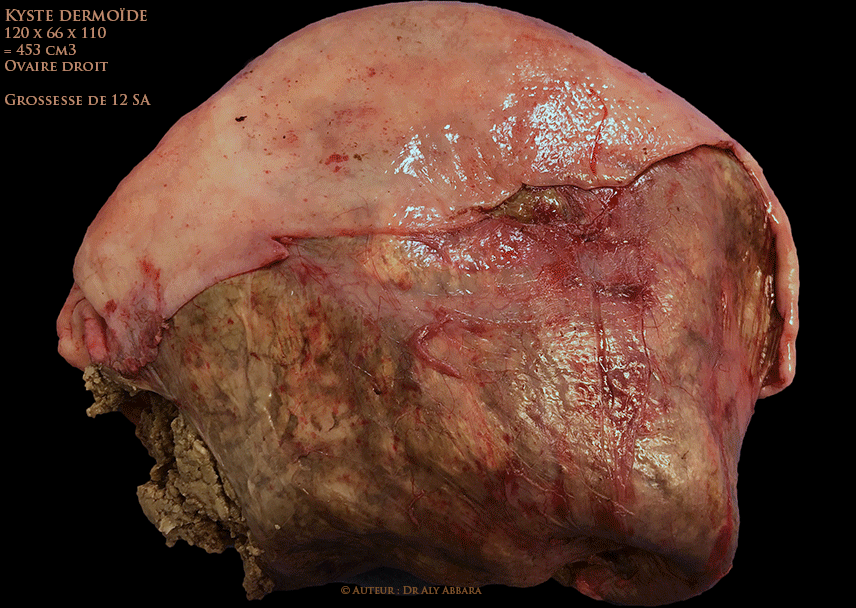

Volumineux tératome bénin de l'ovaire droit (kyste dermoïde) chez une femme enceinte de 12 SA

Série d'images échographiques et macroscopiques montrant les différents aspects et la composition d'un volumineux tératome bénin de l'ovaire droit mis en évidence chez femme enceinte de 12 SA.

L'ovaire droit est d'aspect tumoral, mesurant environ 12-14 cm de grand axe, non adhérentiel, à surface lisse, sans végétation exophytique. Pas d'ascite ni implants péritonéaux tumoraux.

A la coupe anatomopathologique (kystectomie de l'ovaire droit par laparotomie) : il s'agit d'une tumeur uniloculaire évoluant au sein de l'ovaire droit, de consistance pâteuse et à contenu, inhabituel, sableux.